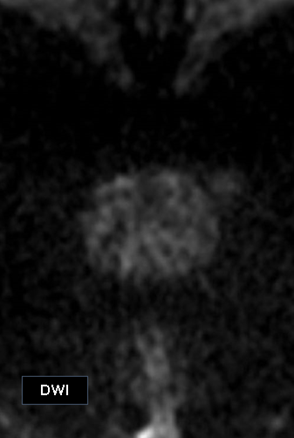

A biparametric MRI (bpMRI) of the prostate demonstrated:

- A 1.11 cm × 0.99 cm lesion in the right posteromedial peripheral zone at the apex.

- T2-weighted: Charcoal/erase-type hypointensity.

- DWI: Hyperintense.

- ADC map: Low signal (restricted diffusion).

The lesion was classified as PI-RADS 4, suggestive of clinically significant cancer.5 There was no evidence of extracapsular extension or seminal vesicle invasion.

MRI findings were suggestive of clinically significant prostate cancer [Turkbey et al., 2019].